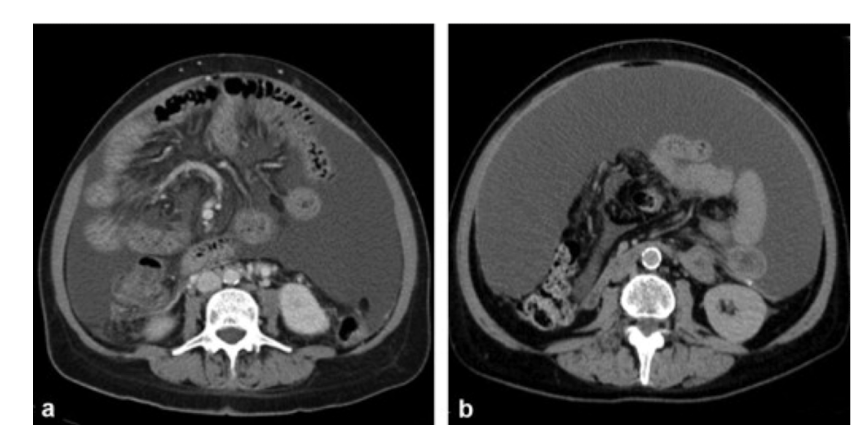

Phase + pathology?

• In PVP as there is opacification of

the portal vein and the liver is also

opacified

• Path = small bowel obstruction

• Small bowel as its characterised by

the ridged lines

• Bowels are dilated and we can’t see

any gas patterns distal to the obstruction.